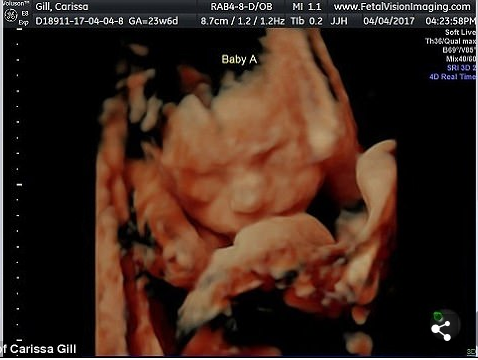

Veja mais fotos do Ultrassom de Carissa: